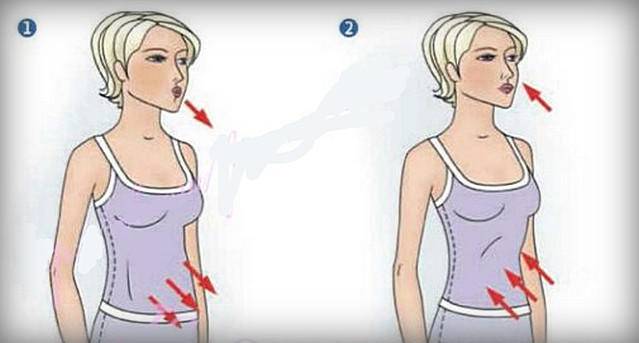

Дыхание через сжатые губы

- Сядьте в кресло и расслабьте мышцы шеи и плеч.

- Медленно вдохните через нос, держа рот закрытым. Вдыхайте в течение 2 секунд.

- Подожмите губы, как будто насвистываете или задуваете свечу. Медленно выдыхайте в течение 4 секунд.

- Повторите дыхание